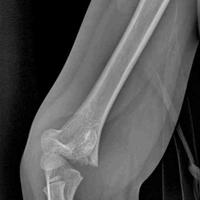

7岁熊孩子肱骨髁上骨折,给他修正。

7岁熊孩子肱骨髁上骨折,给他修正。...